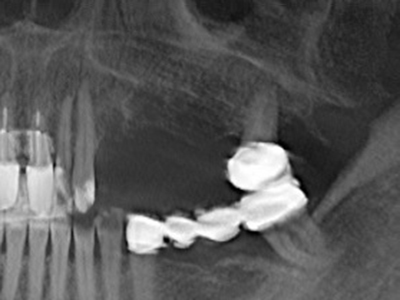

Indicazione: preparazione vicino ai nervi

Come descritto in precedenza, le indicazioni per la piezochirurgia si possono trovare anche nel campo della chirurgia odontoiatrica conservativa. Delle puntine particolari semplificano l'esposizione delle punte delle radici e facilitano la protezione dei nervi e delle membrane mucose del seno, in particolare nella regione dentale superiore e posteriore e in quella premolare inferiore. Le puntine angolate diamantate si utilizzano per preparare con precisione la cavità della resezione che ospiterà il materiale di riempimento della radice retrograda per l'otturazione apicale sigillata. Grazie alla tecnologia a ultrasuoni le puntine possono essere estremamente sottili, quindi la visibilità e le dimensioni di accesso della cavità sono migliori. Di conseguenza, l'applicazione della chirurgia a ultrasuoni per questa indicazione è una delle procedure standard per la resezione apicale (Del Fabbro, Tsesis et al. 2010, Scarano, Artese et al. 2012).

Indicazione: resezione apicale

Quando le procedure chirurgiche vengono eseguite sull'osso nelle immediate vicinanze di strutture sensibili, come vasi sanguigni o nervi, gli strumenti rotanti pongono un rischio significativo di lesione iatrogena. I dispositivi piezoelettrici possono essere utili per la preparazione delle coperture ossee e la rimozione del tessuto duro in prossimità dei nervi, in particolare per la loro esposizione dopo una lesione iatrogena, ma anche durante la lateralizzazione dei nervi per le procedure di resezione e ricostruzione o il posizionamento di impianti (figg. 17-20). Il contatto leggero tra puntina piezoelettrica e nervo non causa generalmente danni, ma se si procede senza prestare attenzione con movimenti a sega o raccordi con residui di substrati ossei possono verificarsi danni al nervo temporanei o anche permanenti. Il rischio di danno, tuttavia, è considerato sostanzialmente inferiore al rischio presente utilizzando seghe o frese (Pereira, Gealh et al. 2014).